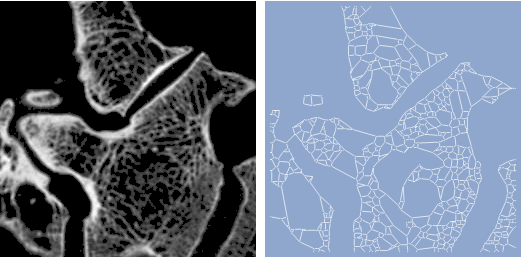

Building a graph of a trabecular bone structure using the

MorphologicalGraph

function in

Mathematica

8.

graph = MorphologicalGraph[ ColorNegate[Image[WatershedComponents[image]]], GraphStyle -> "BackgroundBlue", ImageSize -> {256, 256}];

Row[{image, Spacer[9], graph}]